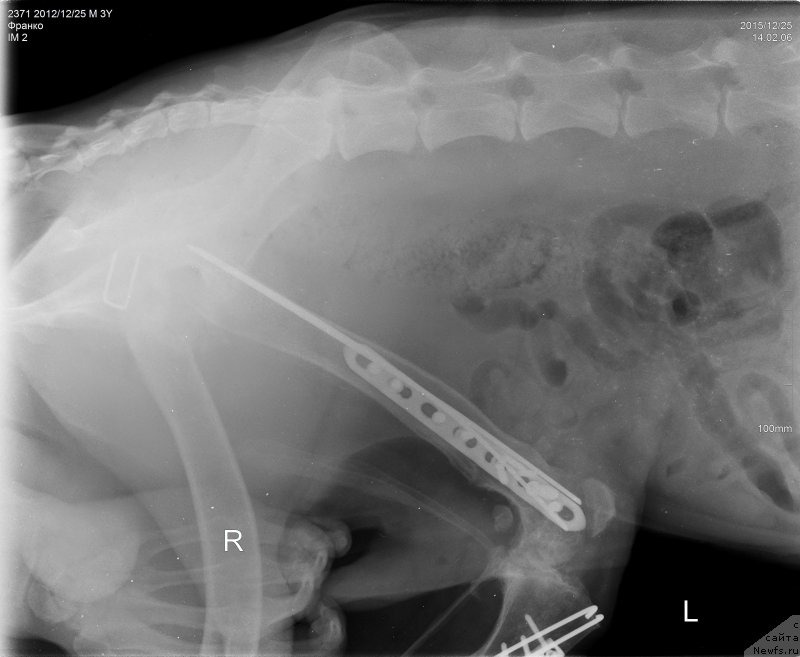

2015.12.25.=Франко снимки бедро латер

Фотография № 198290

2015.12.25.=Франко снимки голень

Фотография № 198291

2015.12.25.=Франко снимки таз ВД

Фотография № 198292

Сергей Александрович написал что абсцесс в мягких тканях а не в надкостнице, как нам озвучили на рентгене.

Ну и артроз коленного сустава.

Пластину на голени надо удалять.

Артроз у Франко ужаснейший.

Хуже мне кажется уже и быть не может.

Ноги Франко так устроены, что он сам их разбивает.

Это чудо , что он еще на ногах,

Нужно чтоб пластины стояли как можно дольше.

Чудо, что Франко на ногах, радуйтесь каждому месяцу.

Это нам написала наша врач.